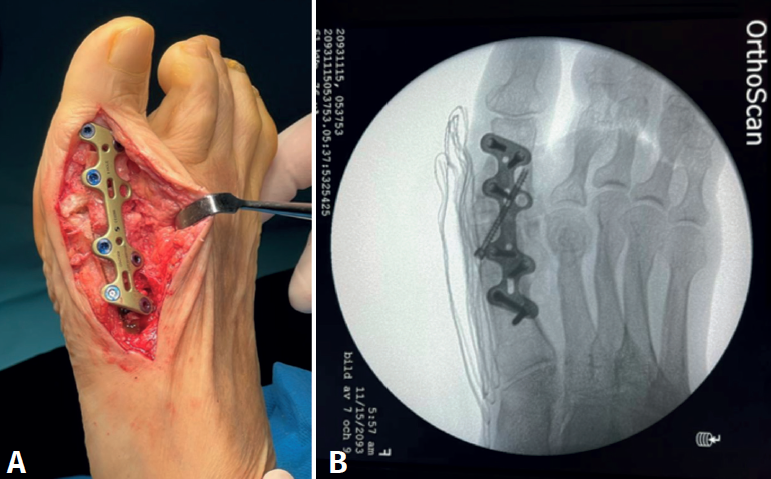

Se utilizó una sierra motorizada para la extracción del injerto corticoesponjoso. La parte cortical es un rectángulo dibujado en la superficie dorsal del primer metatarsiano y de sección triangular (Figura 3). Se realiza una extracción con forma similar en el dorso de la primera falange (Figura 4). Esto genera una cavidad en forma de cuña desde el primer metatarsiano hasta la primera falange (Figura 5). A continuación, el injerto obtenido del primer metatarsiano se moviliza distalmente y se encastra en la cavidad ósea, tendiendo un puente entre los dos huesos (Figura 6). La posición del dedo del pie se evalúa contra una superficie plana para simular la situación de soporte de peso, como en una artrodesis estándar. Se colocan agujas de Kirschner para estabilizar provisionalmente la MTF1. Para rellenar el hueco óseo proximal del primer metatarsiano puede utilizarse el hueso extraído de la falange o un sustituto óseo. Se realizó una fijación con placa de bloqueo dorsal de la MTF1 y con al menos un tornillo de compresión interfragmentaria (Figuras 7 y 8). Se realizó una cirugía simultánea en los dedos menores cuando estaba indicado. La herida se cerró y se vendó de la forma habitual. En caso de deformidad asociada del primer dedo en valgo, se extrajo una cuña ósea de localización supramaleolar interna que se añadió a la reconstrucción previa (Figura 9).